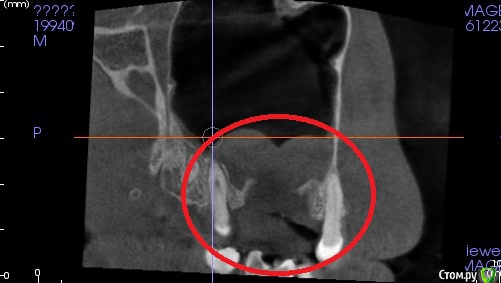

red_butler Опубликовано 30 ноября, 2016 Поделиться Опубликовано 30 ноября, 2016 Делайте Кт с захватом придаточных пазух носа. 1 Ссылка на комментарий

kyzykty1894 Опубликовано 28 декабря, 2016 Автор Поделиться Опубликовано 28 декабря, 2016 Делайте Кт с захватом придаточных пазух носа.Здравствуйте! Я сделал КТ, но никак не могу загрузить сюда Ссылка на комментарий

red_butler Опубликовано 29 декабря, 2016 Поделиться Опубликовано 29 декабря, 2016 сколько времени прошло после операции? Сообщение с синусом устранено полностью? Какое либо консервативное лечение в настоящее время проводится (капли-спрей)? Ссылка на комментарий

kyzykty1894 Опубликовано 29 декабря, 2016 Автор Поделиться Опубликовано 29 декабря, 2016 сколько времени прошло после операции? Сообщение с синусом устранено полностью? Какое либо консервативное лечение в настоящее время проводится (капли-спрей)?Здравствуйте, вот к сожаланию там есть свищевой вход, я второй раз его зашивал, но она открылась, терерь могу попасть после праздников. А этот свищевой вход не закроется сама? Ну вдруг мясо выростит, или я навиный человек Ссылка на комментарий